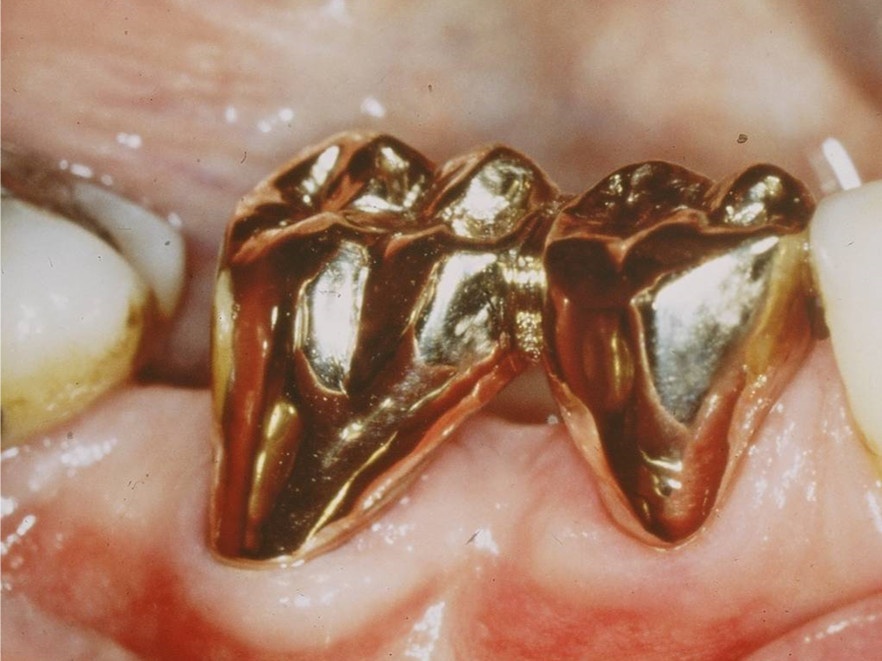

Ziel ist es, durch die Entfernung von Gewebs- und/oder Zahnanteilen die Zugänglichkeit zu schwer zugänglichen parodontalen Defekten zu verbessern. Darüber hinaus kann durch diese Maßnahmen die Hygienefähigkeit verbessert und eine Neubesiedelung des Parodontiums durch die mikrobielle Plaque verhindert werden. Vor allem die Prognose von furkationsbeteiligten Molaren kann auf diese Weise deutlich verbessert werden. In einer vielbeachteten Studie aus dem Jahre 2001 haben Fugazotto und Mitarbeiter die Prognose von 701 resektiv behandelten Molaren untersucht und beeindruckende Ergebnisse erzielt. Nach 15 Jahren waren noch 678 Molaren (94,9 %) in situ und erfüllten die vorgegebenen Erfolgskriterien. So lautete dann auch die Kernaussage dieser Studie, dass bei richtiger Indikationsstellung resektiv behandelte Molaren mindestens die gleich gute Langzeitprognose wie Implantate haben. In diesem Zusammenhang sei erwähnt, dass die Voraussetzung für eine erfolgreiche resektive Therapie die erfolgreiche endodontische Behandlung ist. Wie später noch ausgeführt wird, haben sich gerade auf diesem Gebiet durch technische Neuerungen völlig neue Möglichkeiten ergeben, was die Prognose der resektiv behandelten Molaren weiter verbessern dürfte. Ein kleines Beispiel, wie durch derartige Behandlungsschritte eine Implantation verhindert werden kann, zeigen die Abb. 5 und 6, wo durch eine Hemisektion des mesialen Wurzelanteils am Zahn 46 und anschließende Versorgung mit einer kleinen Brücke von 45 auf 46 eine Implantatinkorporation unnötig wurde.

Idealerweise können mit den Maßnahmen der regenerativen Parodontalchirurgie durch Entzündungen verloren gegangenen Anteile des Parodontiums wiederhergestellt werden. Dazu stehen verschiedene Operationsverfahren zur Verfügung. Einen wissenschaftlich belegten Behandlungserfolg bieten insbesondere Maßnahmen der gesteuerten Geweberegeneration (GTR, Guided Tissue Regeneration) und die Anwendung von Schmelzmatrixproteinen. Da ein Erfolg dieser Maßnahmen ganz maßgeblich von der Defektmorphologie abhängig ist, gilt es eine strenge Indikationsstellung zu beachten. Als prognostisch günstig gelten dreiwandige vertikale Knochendefekte sowie Furkationsdefekte des Grades 2 bei Unterkiefermolaren. Bei der Anwendung der gesteuerten Geweberegeneration können verschiedene Barrieremembranen zum Einsatz kommen. Diese verhindern im Idealfall eine Besiedlung des Defekts mit den schnell proliferierenden Zellen des Epihels oder Bindegewebes und ermöglichen so eine Regeneration mit der Neuausbildung parodontalen Attachments. Eine Therapie mit gesteuerter Geweberegeneration ist technisch durchaus anspruchsvoll und sollte daher nur von parodontalchirurgisch geübten Operateuren angewendet werden. Der Erfolg einer solchen Maßnahme ist in den Abb. 7 und 8 dargestellt. Mittels einer ePTFE-Membran konnte der mesiale vertikale Defekt zur Ausheilung gebracht werden und zeigte sich auch nach fünf Jahren stabil. Vergleichbar gute Erfolgsraten können auch mit der Anwendung von Schmelzmatrixproteinen erzielt werden. Hier sei beispielhaft auf die Studie von Sanz und Mitarbeitern aus dem Jahre 2004 verwiesen, wo mit einem Schmelzmatrixprotein ähnlich gute Ergebnisse hinsichtlich dem Attachmentgewinn und der Reduzierung der Sondiertiefen wie mit Membranen erzielt werden konnte. Als vorteilhaft gegenüber Membranen hat sich die signifikant geringere Rate von Komplikationen gezeigt, zudem ist die Anwendung von Schmelzmatrixproteinen technisch deutlich einfacher.